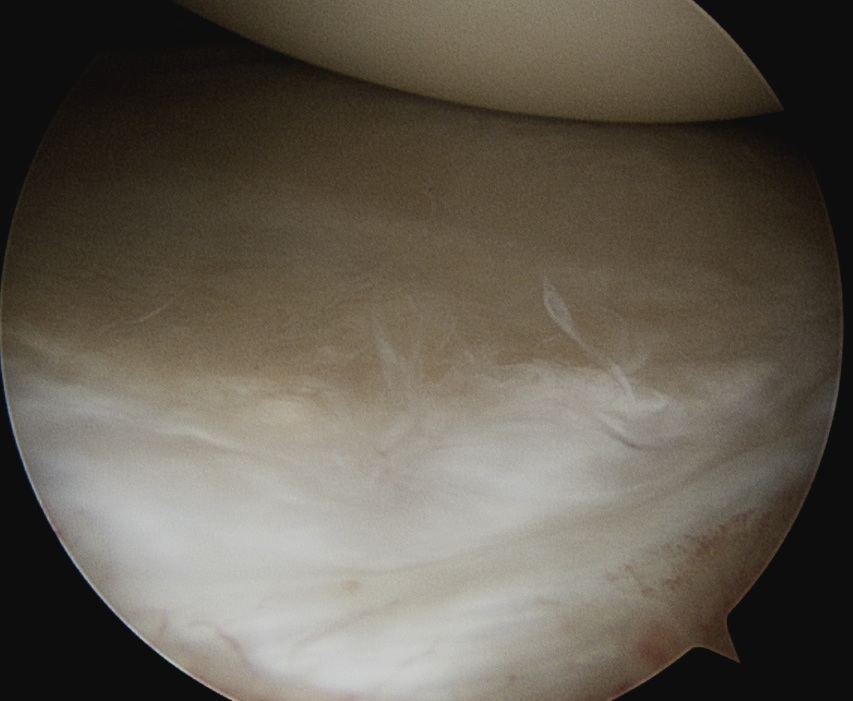

Rotator Interval - triangle of glenoid medial, biceps superior, subscapularis inferior

Humeral head cartilage

Glenoid cartilage

Labrum - anterior / inferior / posterior

Biceps tendon / insertion

Subscapularis

Glenohumeral ligaments

Three thickenings of the glenoid capsule: SGHL, MGHL, IGHL

| Superior glenohumeral ligament (SHGL) | Middle glenohumeral ligament (MGHL) |

|---|---|

|

Origin: Supraglenoid tubercle glenoid and coracoid Insertion: Proximal aspect medial edge lesser tuberosity of the humerus |

Origin: Distal aspect lesser tuberosity of humerus Insertion: Posterior aspect subscapularis |

Runs perpendicular to the middle GHL |

Crosses subscapularis vertically Variable size and shape in different people Cord like / leaf like / vestigal |

Stabilizes the long head of the biceps in its groove Limits external rotation of the humerus |

Limits external rotation with arm by side |

![]() |